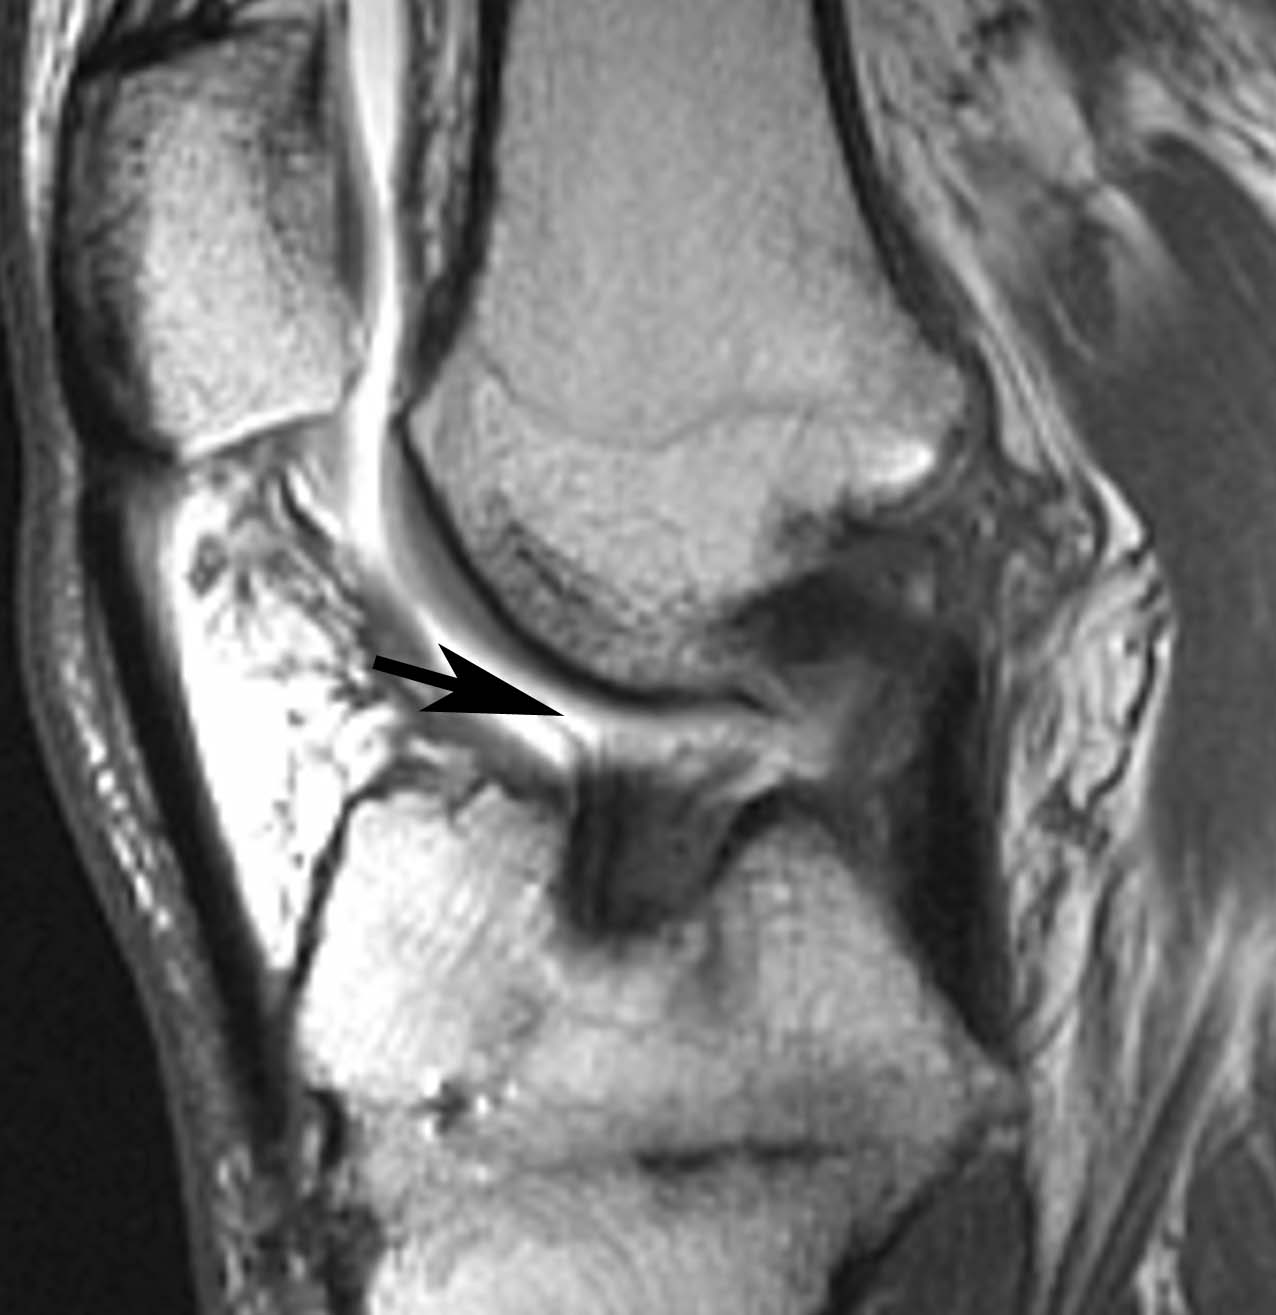

Figure 3 for case Disrupted ACL graft

Figure 3

Discussion

Nice depiction of torn fibers at tibial tunnel with MR arthrography